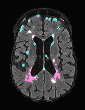

In recent years, data-driven machine learning (ML) methods have revolutionized the computer vision community by providing novel efficient solutions to many unsolved (medical) image analysis problems. However, due to the increasing privacy concerns and data fragmentation on many different sites, existing medical data are not fully utilized, thus limiting the potential of ML. Federated learning (FL) enables multiple parties to collaboratively train a ML model without exchanging local data. However, data heterogeneity (non-IID) among the distributed clients is yet a challenge. To this end, we propose a novel federated method, denoted Federated Disentanglement (FedDis), to disentangle the parameter space into shape and appearance, and only share the shape parameter with the clients. FedDis is based on the assumption that the anatomical structure in brain MRI images is similar across multiple institutions, and sharing the shape knowledge would be beneficial in anomaly detection. In this paper, we leverage healthy brain scans of 623 subjects from multiple sites with real data (OASIS, ADNI) in a privacy-preserving fashion to learn a model of normal anatomy, that allows to segment abnormal structures. We demonstrate a superior performance of FedDis on real pathological databases containing 109 subjects; two publicly available MS Lesions (MSLUB, MSISBI), and an in-house database with MS and Glioblastoma (MSI and GBI). FedDis achieved an average dice performance of 0.38, outperforming the state-of-the-art (SOTA) auto-encoder by 42% and the SOTA federated method by 11%. Further, we illustrate that FedDis learns a shape embedding that is orthogonal to the appearance and consistent under different intensity augmentations.